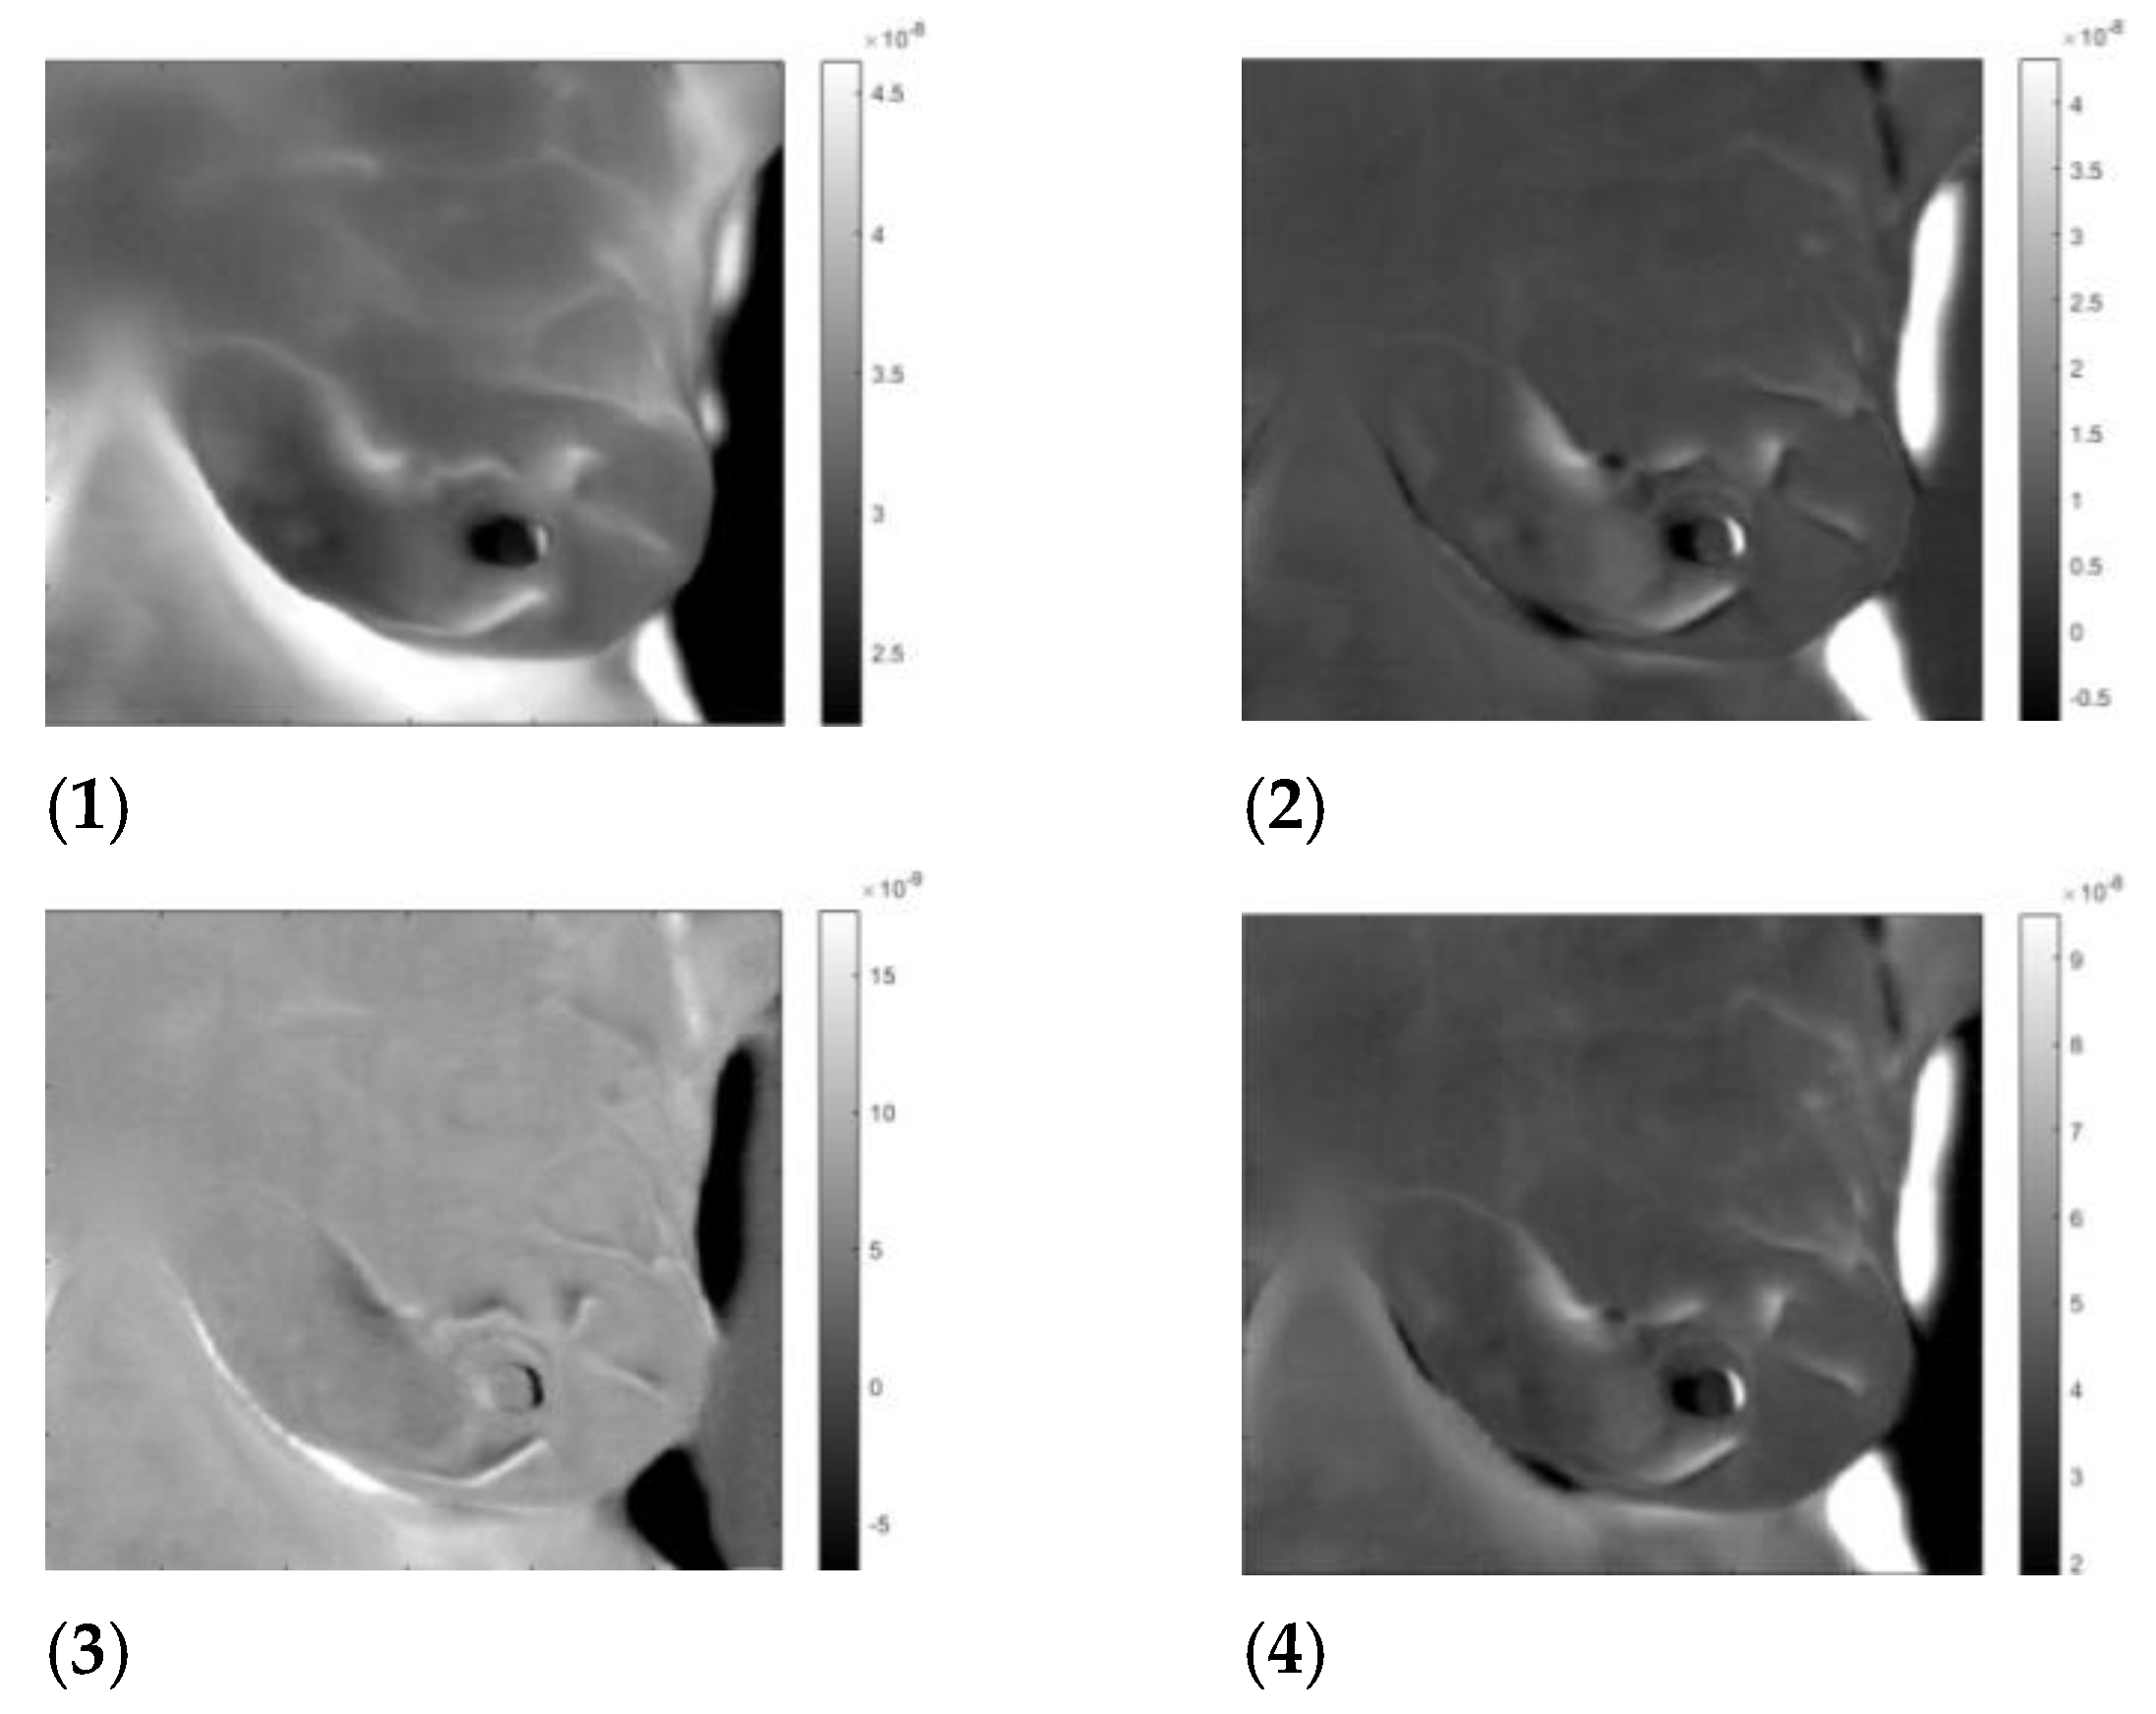

3. Results

3.3. Analysis